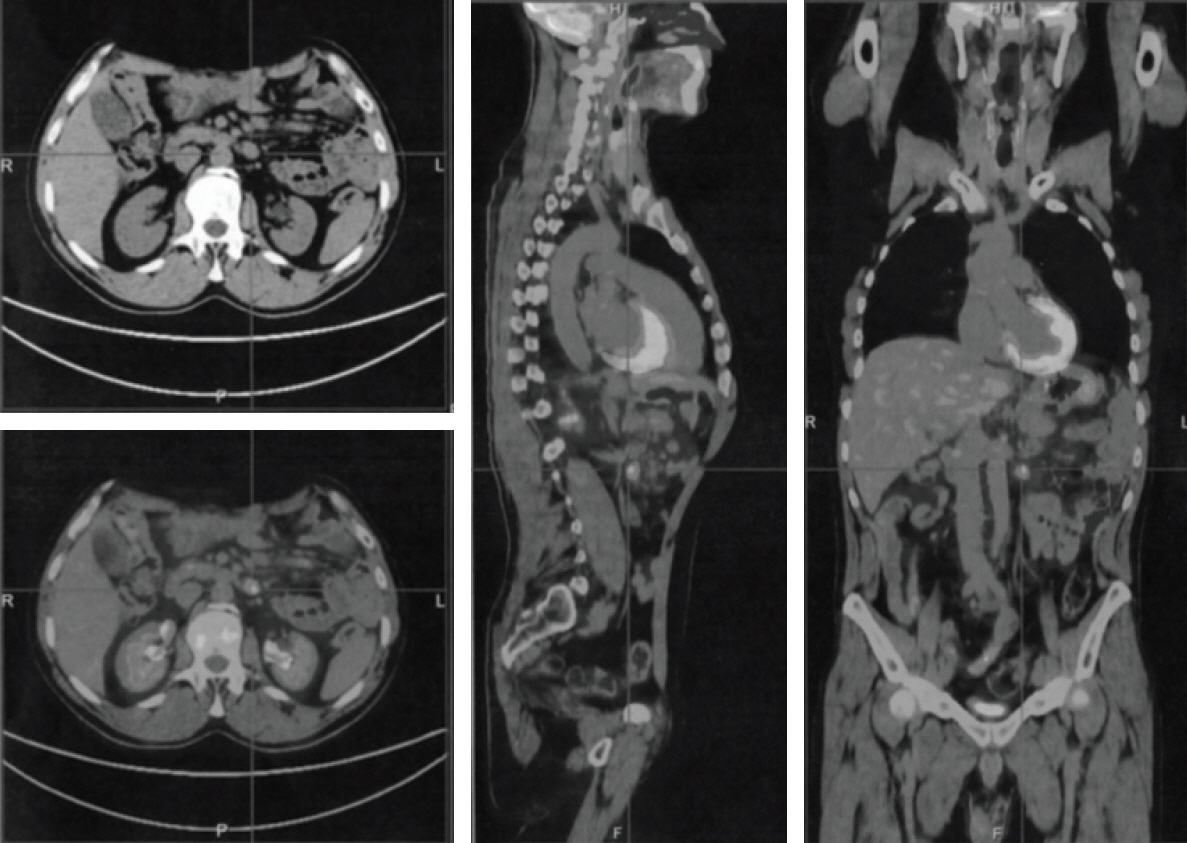

Crohn’s Disease Following Rituximab Treatment for Follicular Lymphoma in a Patient with Synchronous Gastric Signet Ring Cells Carcinoma: A Case Report and Literature Review

- Recently, there have been a few reports of rituximab (RTX)-induced Crohn’s disease, but there is no literature available on successful long-term treatment and the clinical outcome of this condition. We retrospectively analyzed the clinical data of a rare case of Crohn’s disease induced by RTX administered as induction and prolonged maintenance therapy of a follicular lymphoma, diagnosed synchronously with a gastric signet ring cells carcinoma, treated at our hospital.

Figure